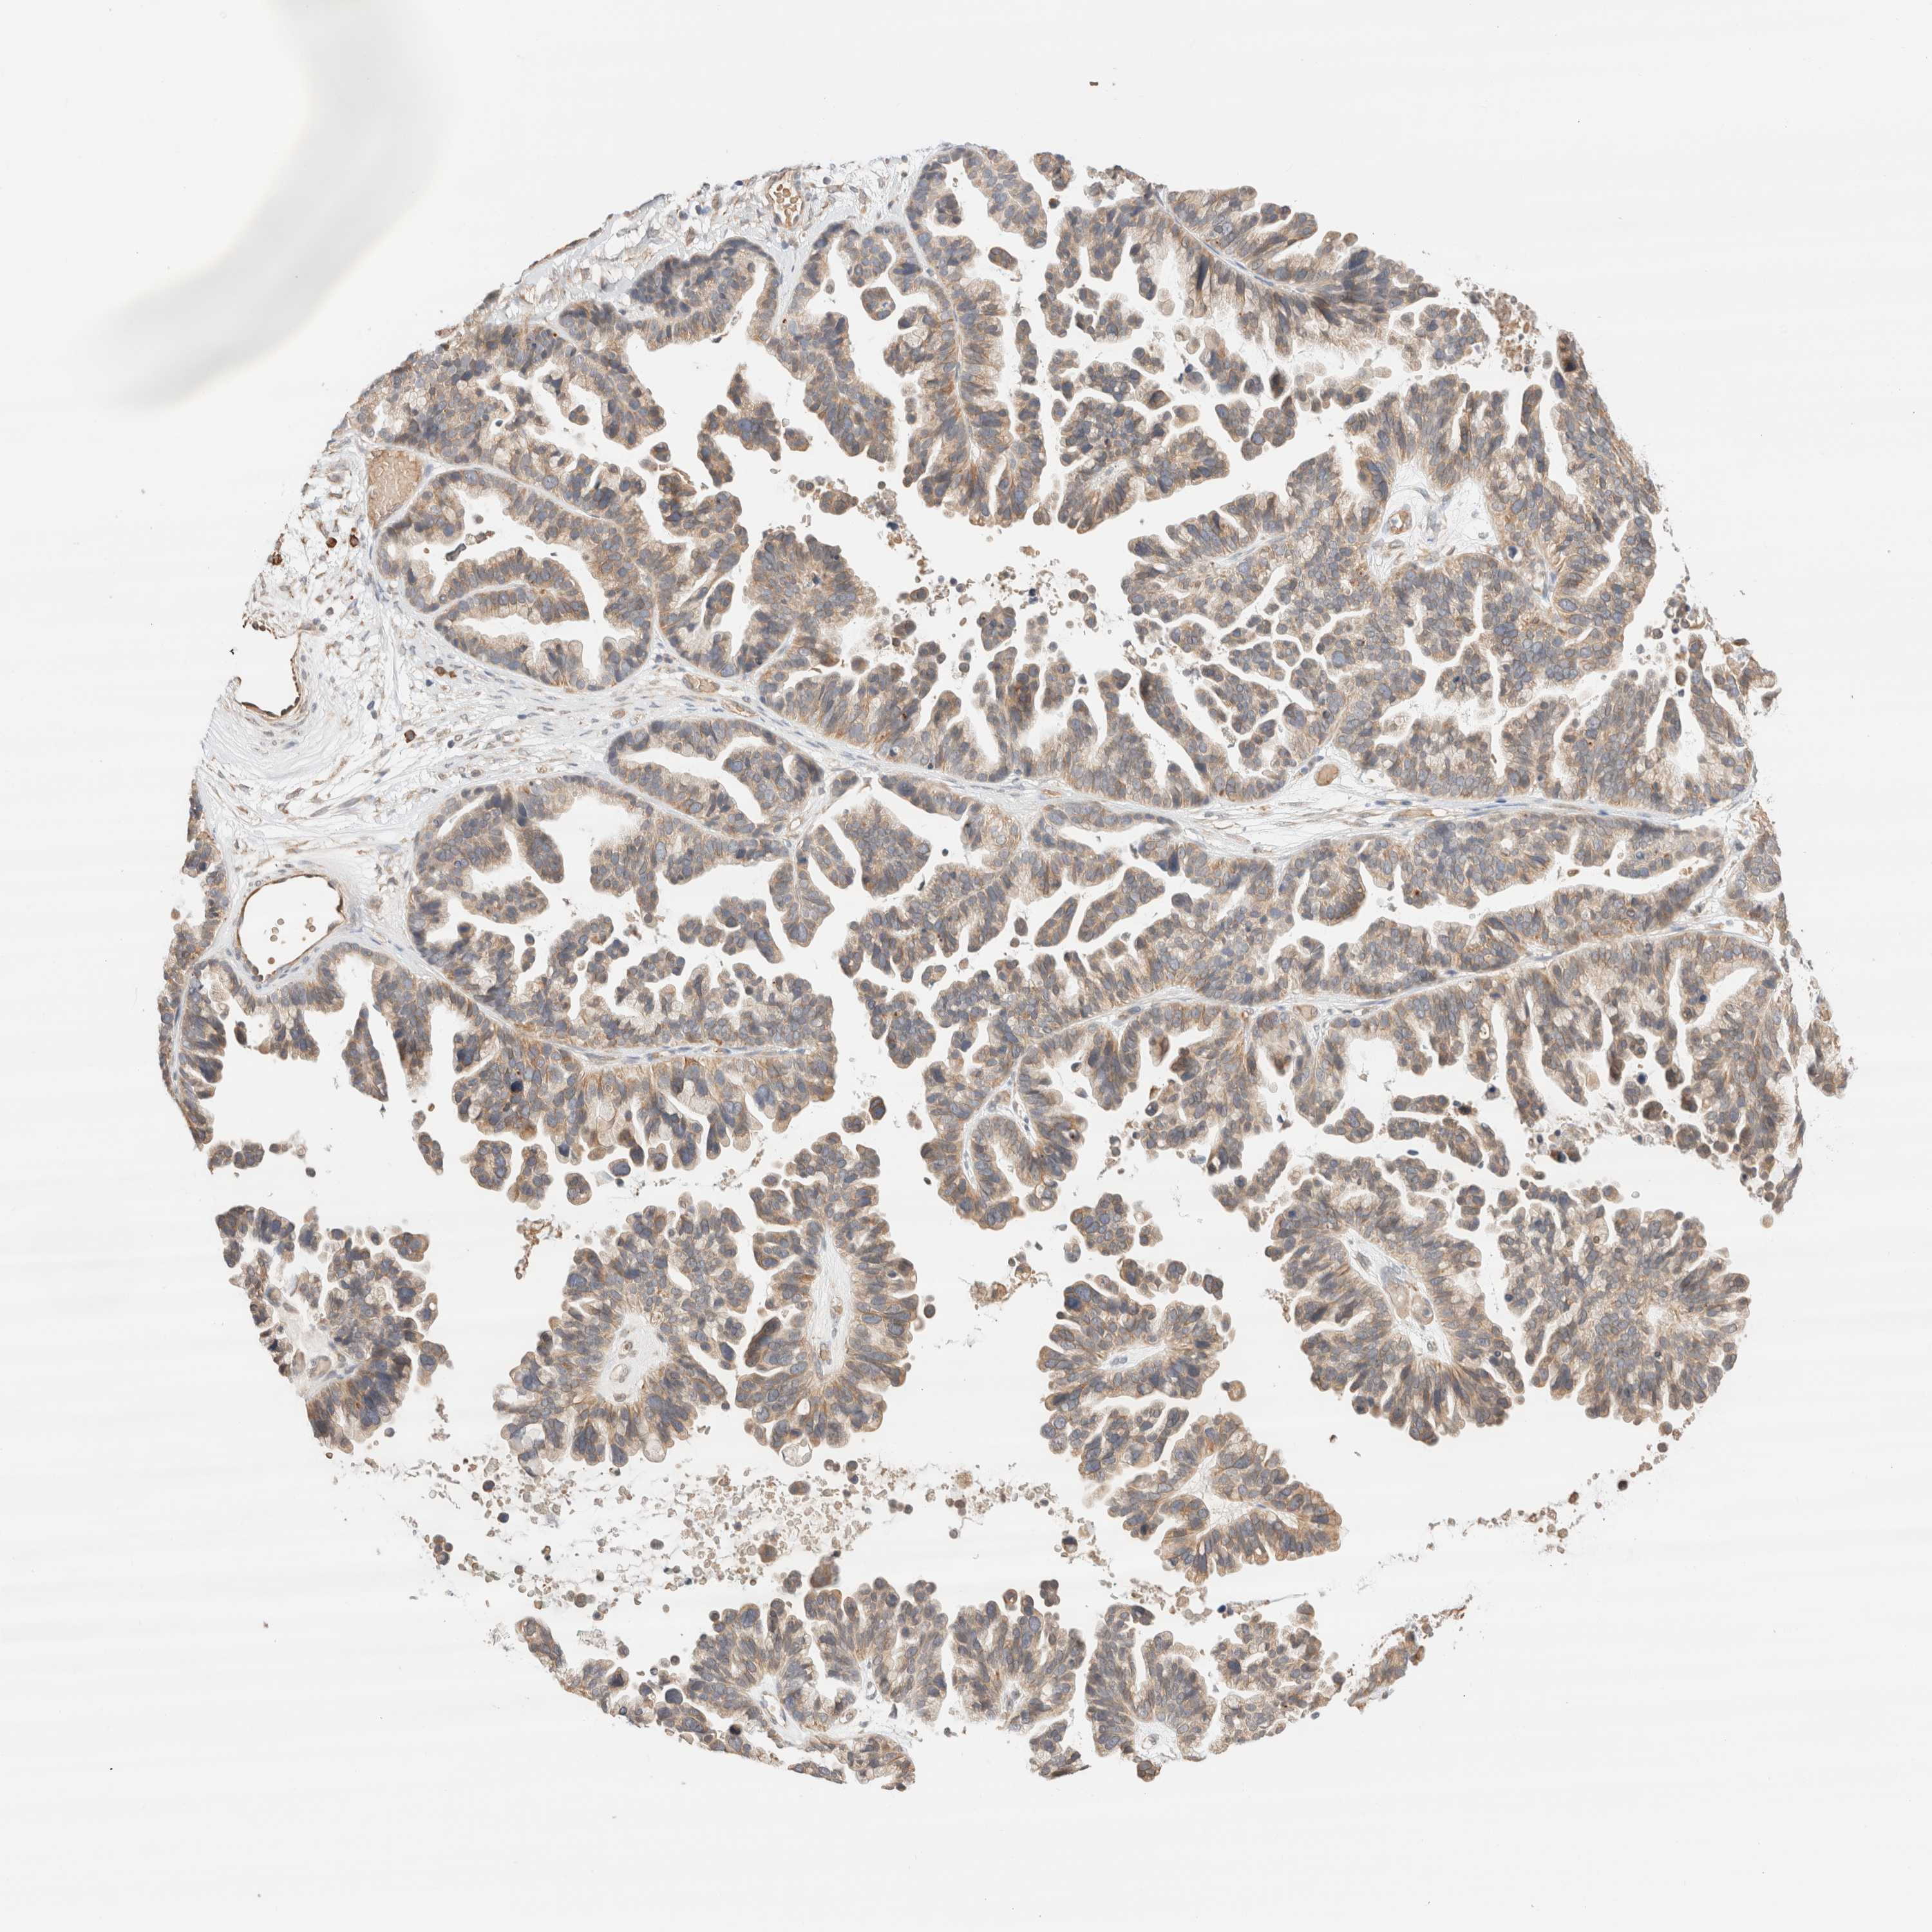

OVARIAN CANCER - Protein expressioni

A mouse-over function shows sample information and annotation data. Click on an image to view it in a full screen mode. Samples can be filtered based on level of antibody staining by selecting one or several of the following categories: high, medium, low and not detected. The assay and annotation is described here.

Note that samples used for immunohistochemistry by the Human Protein Atlas do not correspond to samples in the TCGA dataset.

Antibody stainingi

Antibody staining in the annotated cell types in the current human tissue is reported as not detected, low, medium, or high, based on conventional immunohistochemistry profiling in selected tissues. This score is based on the combination of the staining intensity and fraction of stained cells.

Each image is clickable and will lead to virtual microscopy that enables deeper exploration of all samples and also displays staining intensity scores, fraction scores and subcellular localization as well as patient and tissue information for each sample.

Antibody CAB037030

Staining

Low

Not detected

Cystadenocarcinoma, mucinous, NOS

Carcinoma, NOS

Cystadenocarcinoma, serous, NOS